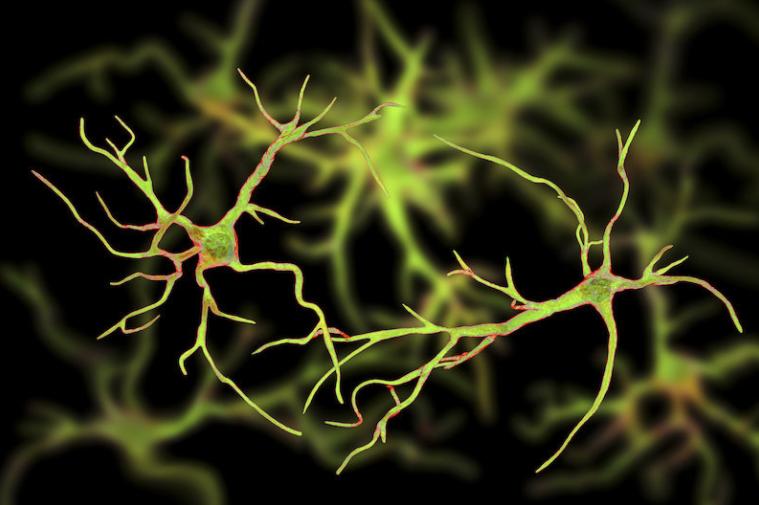

研究人员收集了常规脑手术的新鲜脑组织,对这些脑组织进行切除,并进行多次模拟人死后的间隔。结果,他们就发现,在这些脑组织当中,有一部分细胞中的基因没有停止表达,而且还在增加表达。于是,他们把这些死后还会表达的基因称之为:僵尸基因。这些僵尸基因在人死后大脑的神经胶质细胞当中。(神经胶质细胞的工作主要是:在脑损伤之后,进行清理。)

僵尸基因的表达可以促使神经胶质细胞持续地生长好几个小时,并且长出“长臂状”的附属物。在人死后的12个小时左右达到活性的最高峰。

研究人员介绍,可以帮助科学家更加了解精神分裂症和阿尔茨海默氏病等疾病,甚至有可能给治疗 癫痫症提供新的思路。